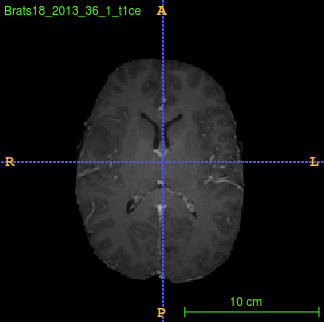

Segmentation of brain tumor from magnetic resonance imaging (MRI) is a vital process to improve diagnosis, treatment planning and to study the difference between subjects with tumor and healthy subjects. In this paper, we exploit a convolutional neural network (CNN) with hypercolumn technique to segment tumor from healthy brain tissue. Hypercolumn is the concatenation of a set of vectors which form by extracting convolutional features from multiple layers. Proposed model integrates batch normalization (BN) approach with hypercolumn. BN layers help to alleviate the internal covariate shift during stochastic gradient descent (SGD) training by zero-mean and unit variance of each mini-batch. Survival Prediction is done by first extracting features(Geometric, Fractal, and Histogram) from the segmented brain tumor data. Then, the number of days of overall survival is predicted by implementing regression on the extracted features using an artificial neural network (ANN). Our model achieves a mean dice score of 89.78%, 82.53% and 76.54% for the whole tumor, tumor core and enhancing tumor respectively in segmentation task and 67.90% in overall survival prediction task with the validation set of BraTS 2018 challenge. It obtains a mean dice accuracy of 87.315%, 77.04% and 70.22% for the whole tumor, tumor core and enhancing tumor respectively in the segmentation task and a 46.80% in overall survival prediction task in the BraTS 2018 test data set.